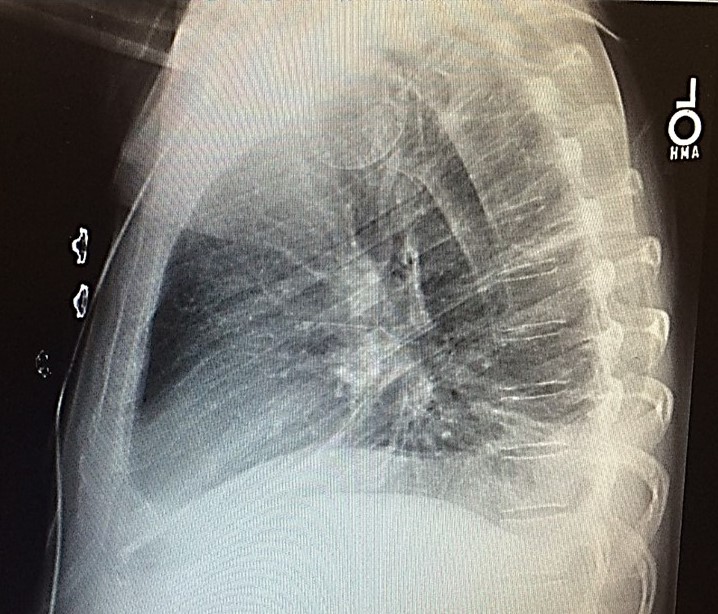

Because of the COVID19 pandemic, you are practicing telemedicine. You are shown the

chest x-rays and an EKG of a 65-year-old man who is complaining of shortness of breath.

DIAGNOSIS: S1Q3T3 pattern in a patient with pulmonary embolism (note the right lower

lobe infiltrate in the PA film and the wedge-shaped infiltrate in the lateral film).